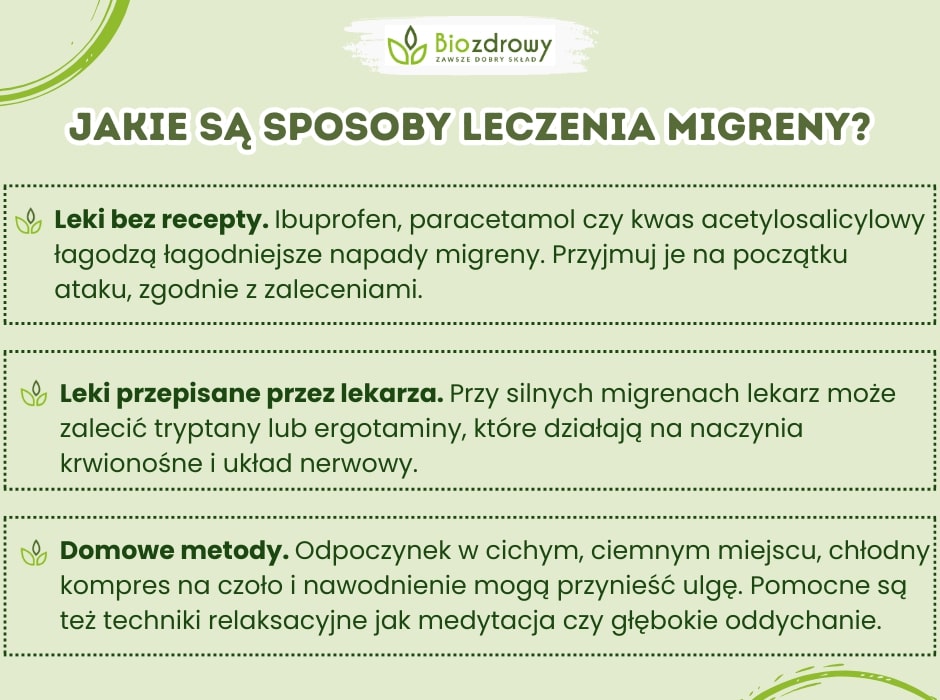

Leczenie migreny opiera się na łagodzeniu objawów podczas napadu oraz na stosowaniu metod, które mogą zmniejszyć ich częstotliwość i nasilenie. Warto zapoznać się z różnymi formami terapii, aby dobrać odpowiednie rozwiązania dostosowane do swoich potrzeb.

Leki przeciwbólowe bez recepty

Przy łagodniejszych migrenach można stosować dostępne bez recepty leki przeciwbólowe, takie jak ibuprofen, paracetamol czy kwas acetylosalicylowy. Ich skuteczność jest najwyższa, gdy zostaną przyjęte na samym początku napadu. Pamiętaj jednak, aby nie przekraczać zalecanych dawek i nie stosować ich zbyt często, ponieważ mogą wywołać tzw. bóle głowy z odbicia.

Leki na migrenę przepisane przez lekarza

W przypadku silniejszych migren lub jeśli leki bez recepty nie przynoszą ulgi, warto skonsultować się z lekarzem, który może przepisać specjalistyczne leki, takie jak tryptany lub ergotaminy. Tryptany działają bezpośrednio na naczynia krwionośne i układ nerwowy, łagodząc ból migrenowy i towarzyszące mu objawy. Wymagają jednak recepty i powinny być stosowane zgodnie z zaleceniami lekarza.

Domowe sposoby na migrenę

W trakcie napadu migreny pomocne mogą być również metody domowe. Ciemne, ciche pomieszczenie, chłodny kompres na czoło i odpoczynek mogą pomóc złagodzić ból. Warto także zadbać o odpowiednie nawodnienie organizmu. Niektórym osobom ulgę przynoszą techniki relaksacyjne, takie jak głębokie oddychanie lub medytacja, które pomagają zmniejszyć napięcie mięśni i obniżyć poziom stresu.